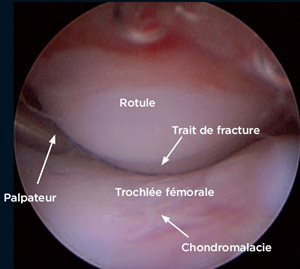

L’exploration articulaire commence généralement par la rotule [1] : sa face articulaire est complètement explorée, un crochet palpateur peut être introduit afin d’estimer la qualité du cartilage, de

rechercher une fracture ou une fissure (Photo 1).

On peut également juger la morphologie de la trochlée fémorale, et choisir la correction chirurgicale adaptée lors de luxation rotulienne.

Photo 1 - Fracture transverse de la rotule.